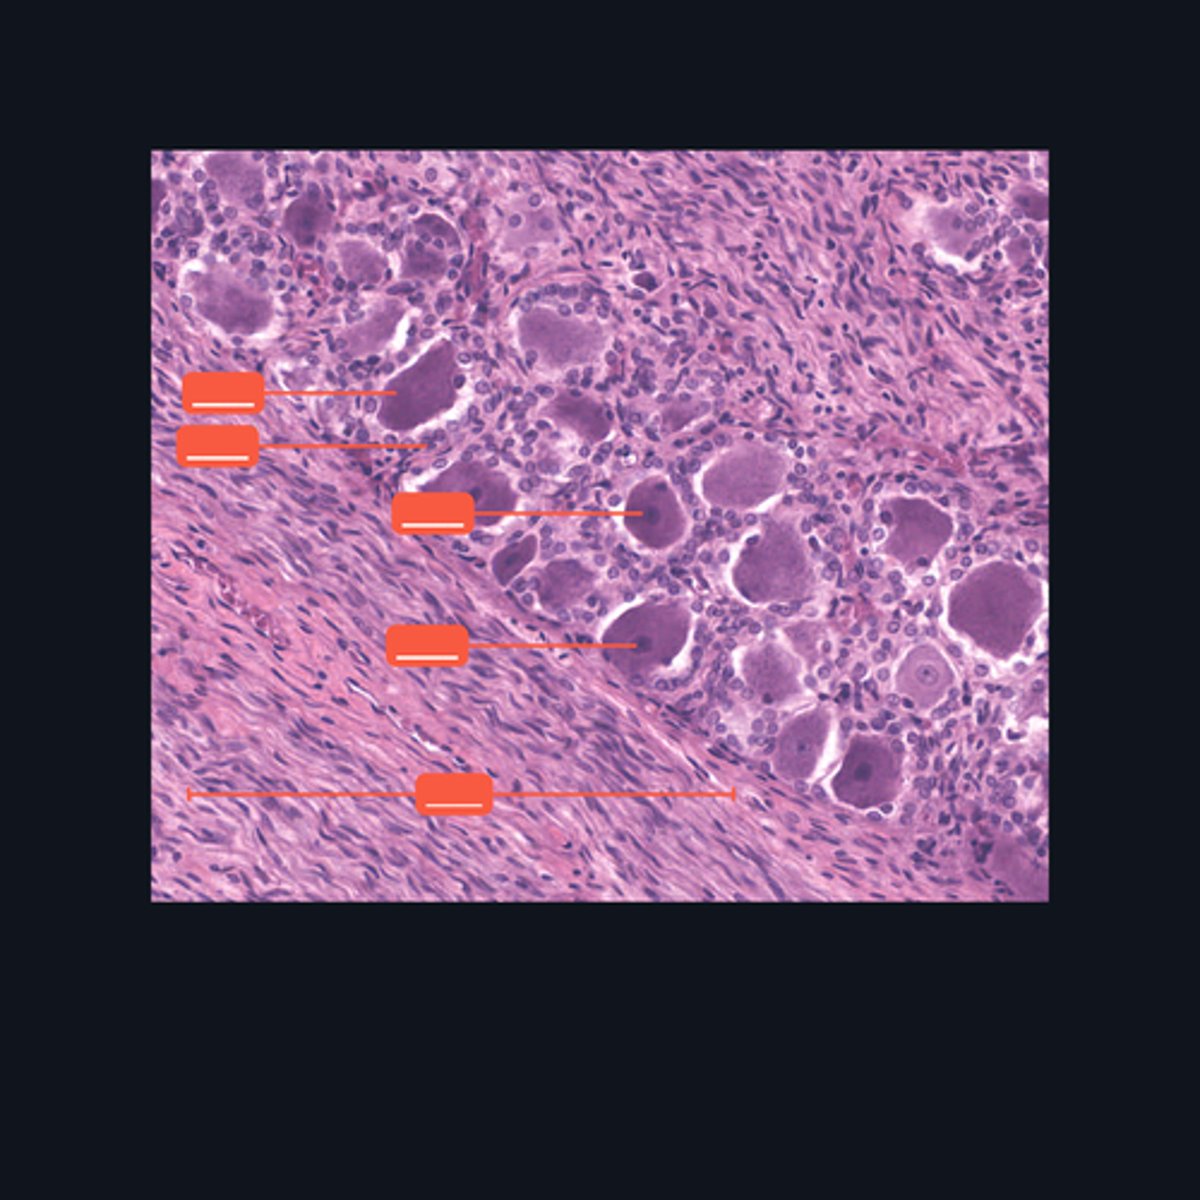

Dorsal root ganglion and nervous tissue

Identify the specific structure given in the image, as well as the type of tissue predominating in the structure.

(top to bottom)

Somatic sensory neurons

Capsule

Identify the structures of the dorsal root ganglion. Be as specific as possible.

(top to bottom)

Cell body

Satellite cell

Nucleus

Nucleolus

Nerve fibers

Identify the parts of the spinal ganglion in high magnification.

False, pseudounipolar

T or F: The neurons that congregate in this structure is multipolar.

(bottom to top)

Capsule

Ganglion Cell

Satellite cell

Nerve fibers

Nucleolus

Nucleus

Nissl Granules

Identify the structures of a sympathetic ganglion.

Multipolar, autonomic motor neurons

What kind of motor neurons are present in this structure?

Dense Irregular Connective Tissue

What kind of tissue is the capsule of a spinal ganglion made up of? Be specific.